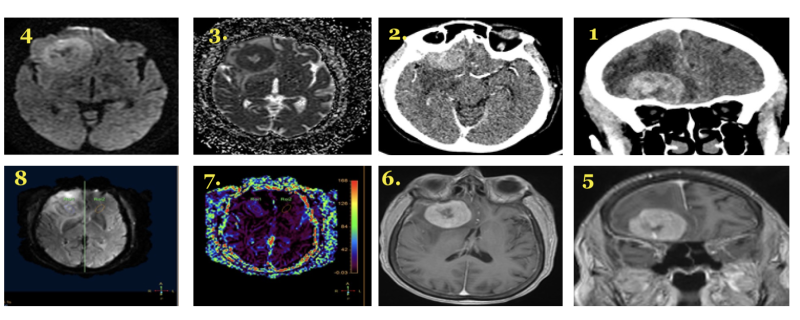

Imaging of CNS Lymphoma